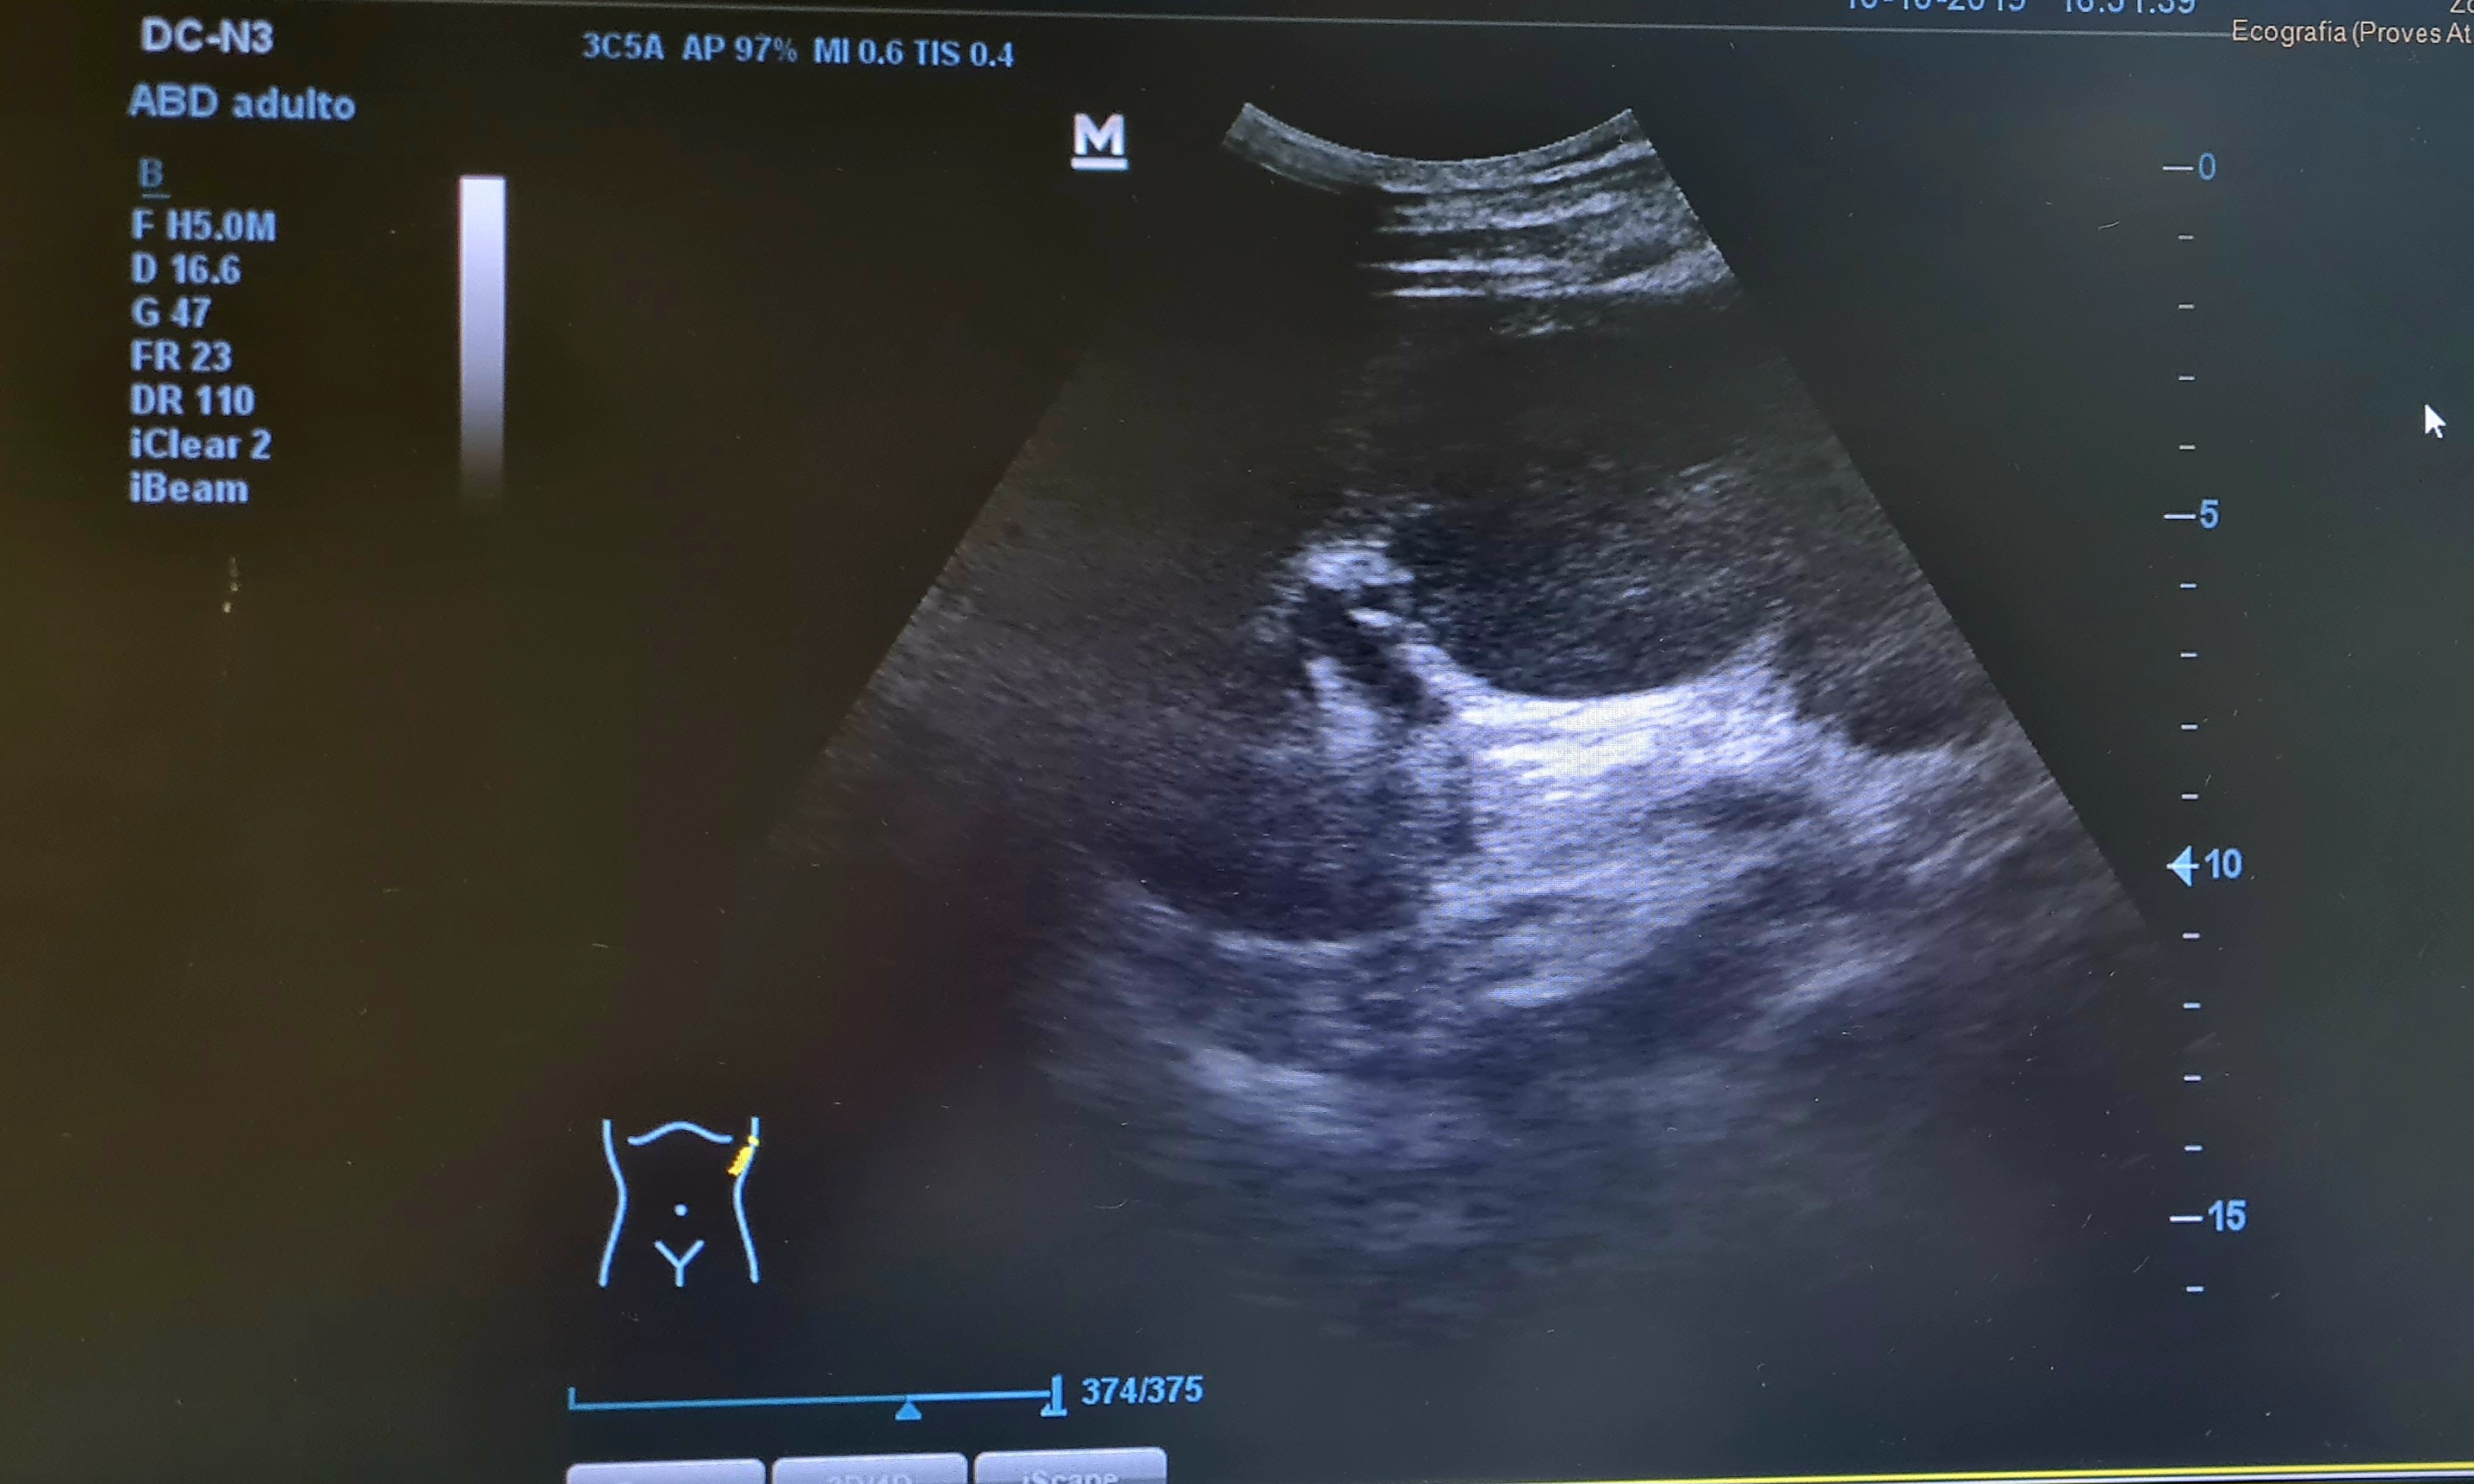

Con el diagnóstico de cólico persistente se practica una ecografía a pie de cama para descartar obstrucción, que muestra una gran masa en hipocondrio Izquierdo, que parece depender de bazo.

Se solicita TC abdominal urgente que informa (día 74): Aumento de tamaño del bazo a expensas de voluminosa lesión nodular sólida y heterogénea con centro hipodenso, siendo de unos diámetros máximos aproximados de 8x10,5x13,5 cm, que se asocia a cambios inflamatorios en la grasa periesplénica inferior. Como primera opción diagnóstica sugiere proceso linfoproliferativo.